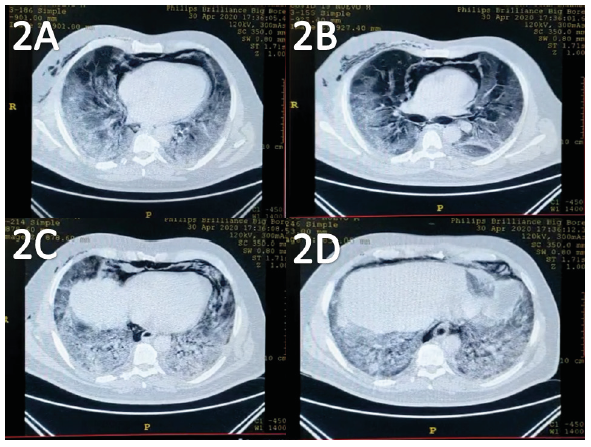

It is noteworthy to emphasize the clinical presentation in patients infected with SARS-CoV-2: symptoms might range from asymptomatic to critical [2]. Radiological findings on undergoing Chest Computed Tomography (CCT) are bilateral peripheral ground-glass opacities with or without consolidations predominantly affecting lower lobes. Less common findings include fine reticular opacities, vascular thickening, reverse halo sign, air bronchogram, interlobular septal thickening, pleural thickening, lymphadeno- pathy, cystic changes, and pleural effusion [1].

Imaging: an urgent chest computed tomogra- phy was requested and showed subcutaneous emphysema (Figure 1), bilateral ground-glass opacities with peripheral distribution, also air into the hilum and pericardic pleura (Figure 2).